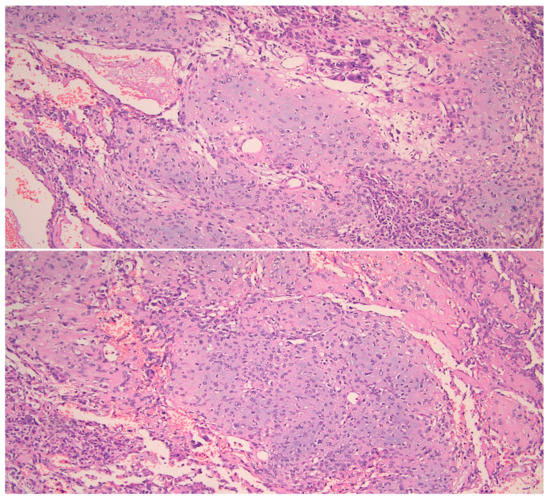

On gross pathology examination, the left ovary measured 4.5 × 3 × 2 cm, showing an intact, smooth outer surface. The cut section revealed a small unilocular cyst with an adjacent large, solid mass. The left Fallopian tube and the uterus were grossly normal. The omentum presented multiple nodules, the largest of which measured 4 cm. The resected large bowel segment showed a 5 cm nodule on the serosal surface. Histologically, the left ovary showed a serous cystadenoma, undergoing progressive transition to a serous borderline tumor and invasive carcinoma (Figure 1). The invasive part showed focal histological features of low-grade serous carcinoma (10%), but was mainly composed of a mesonephric-like adenocarcinoma (85%), showing tubular, glandular (pseudoendometrioid), sex cord-like and solid patterns (Figure 2). The tubular structures lumens contained typical eosinophilic colloid-like secretions. The nuclei were monomorphic, predominantly with vesicular chromatin and inconspicuous nucleoli. Focal lymphovascular invasion was present. There were no squamous or mucinous elements. However, a part of the neoplasm showed a chondrosarcomatous component (5%), intermingled with carcinomatous elements (Figure 3). The chondrosarcomatous component was observed also in the intestinal nodule, along with glandular and solid carcinomatous elements, infiltrating from the visceral peritoneum into the pericolic fat. The omental and peritoneal nodules revealed the same histological features as the ovarian mesonephric-like adenocarcinoma, without sarcomatous differentiation.

Figure 2. Mesonephric-like adenocarcinoma showing different patterns. (HE, 200×).

The histological features of these tumors are peculiar. They usually show an admixture of different architectural patterns, such as tubular, glandular (variously sized), papillary, sex cord-like, slit-like, retiform and solid. The tubular and glandular patterns are the most common and often contain typical intraluminal secretions, composed of eosinophilic colloid-like material. The tumor cells show a variable shape and size, usually with a scanty eosinophilic cytoplasm and monotonous hyperchromic or vesicular nuclei [5,16]. The case herein presented showed a predominant carcinomatous component with histological features of mesonephric-like adenocarcinoma, associated with a low-grade serous carcinoma component, arising from an ovarian serous cystadenoma. These interesting histological features are in accordance with other cases in literature, demonstrating the association of mesonephric-like adenocarcinomas with other ovarian neoplasms, and may offer further proof of the possible Müllerian origin of these tumors.